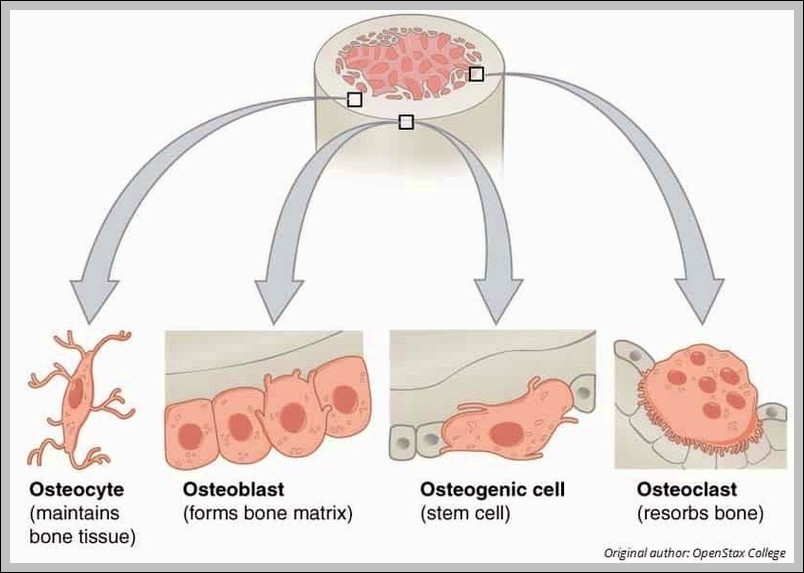

Cellular Components of Bone Diagram

The Cellular Components of Bone diagram zooms to the microscopic level with osteoblasts building matrix, osteocytes living inside lacunae, osteoclasts breaking bone down, and the osteon units with their central…